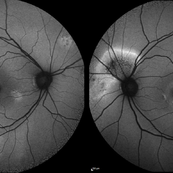

Color fundus montage of an 13-year-old female with arteriovenous malformation (Wyburn Mason Racemose Angiomatosis) affecting her right eye. The retinal arteriovenous malformation appears to be stable. She presented with NLP in the eye, strabismus, and peripheral retinal ischemia. She is at risk for neovascular complications; however, she is currently being treated with Sirolimus. Since she is on this systemically, there is no need to perform intraocular anti-VEGF injections or PRP laser. She also presented with optic atrophy affecting her left eye, secondary to chiasmal involvement of arteriovenous malformation. She has had a potential progressive visual field loss involving the temporal aspect of her visual field from the left eye. There is sector optic atrophy. Presumably, this is due to a compressive effect of her arteriovenous malformation on the nasal nerve fiber layer (corresponding to the temporal visual field) crossing to the right occipital cortex at the chiasm.

Photographer: Olivia Rainey

Imaging device: Topcon 50dx

Condition/keywords: arteriovenous malformation, color fundus photograph, color photo, montage, peripheral ischemia, Sirolimus